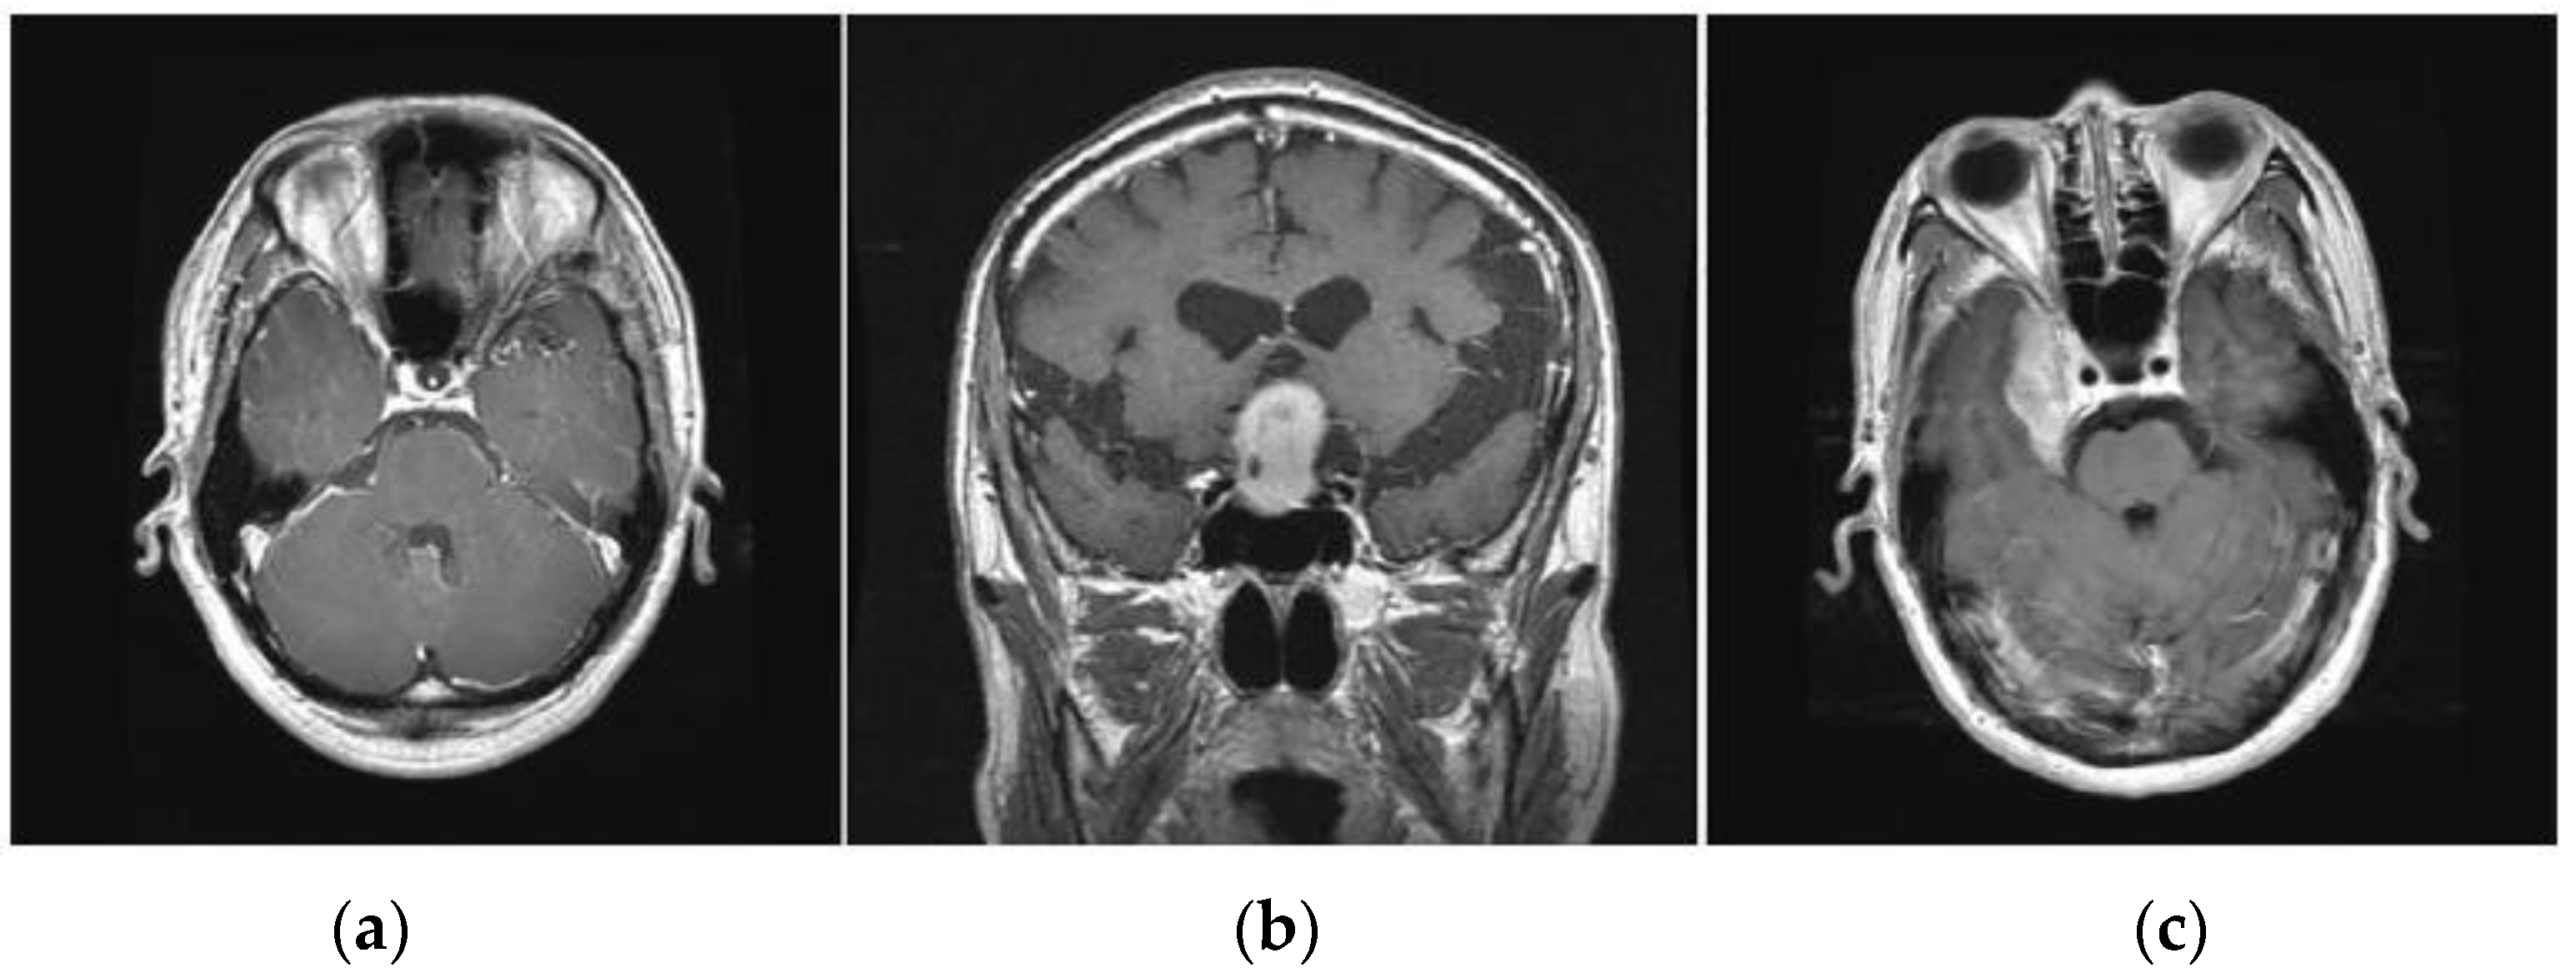

Figure 2.

Various types of brain tumors (a) Glioma (b) Pituitary (c) Meningioma.

Gliomas are positioned within the cerebral hemispheres; however, they may also appear in certain parts of the human brain. Pituitary tumors are positioned within the sella turcica, a minor depression within the skull that covers the pituitary gland. Meningiomas are positioned within the meninges, the membranes that cover the brain as well as the spinal cord.